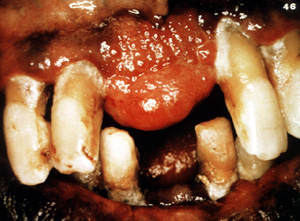

Éste es un ejemplo bastante típico de una lesión  nodular, firme cubierta por  epitelio normal. El color indica que hay proliferación vascular.

Este ejemplo típico se ulcera focalmente pero es asintomático. Este varón de 48 años de edad declaró que la lesión se había estado agrandando durante 5 años. Los dientes aparecen separados. Es frecuente  que estas lesiones pueden ser bastante agresivas y pueden cambiar de sitio a los dientes.

Esta gran lesión se extendió bien en lingual y cambió de sitio algunos de los dientes. Los granulomas periféricos lograrán un tamaño considerable sin tratamiento. La terapia es la biopsia por escisión . Puede ser necesario extender la cirugía  al hueso subyacente para eliminar la lesión. También se indica la eliminación de estímulos irritantes.

Este fibroma  periférico se proyecta desde la encía y se muestra enrojecido. Parece un granuloma.